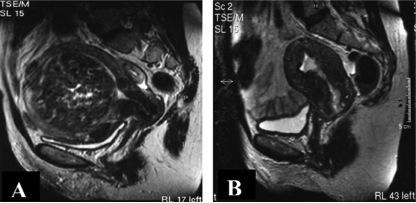

粘膜下子宫肌瘤经宫颈排出率发生率究竟有多少?回顾性研究评价粘膜下子宫肌瘤栓塞后的20例患者,子宫肌瘤排出的危险【3】。50%患者栓塞后体验到子宫肌瘤经宫颈排出的过程。被排出的子宫肌瘤平均容积是56.8ml,没有排出的子宫肌瘤平均容积是123.8cc(P<0.05)。子宫肌瘤≤66.0ml,73%被排出的可能,子宫肌瘤>66.0ml,78%可能不被排出【3】。当宫腔内肿瘤容积非常大的情况下,栓塞可能是一个问题。回顾性复习39例患者,巨大内膜下子宫肌瘤栓塞需要考虑这一栓塞手段的特殊性【4】。1. Bradley EA, et al. Br J Obstet Gynaecol 1998  通过确定肌瘤直径(a→b)与子宫内膜最大界面的比值(x→y→z),评价子宫肌瘤与子宫内膜的关系。13例(33%)粘膜下子宫肌瘤栓塞后为腔内病变(子宫肌瘤腔内脱落)。子宫肌瘤界面比>0.55子宫肌瘤栓塞后更可能成为腔内病变,这一变化的茎直径<45%。多数子宫肌瘤栓塞后脱落腔内,可无症状自发排出;但直径>6cm的子宫肌瘤需要干预。

粘膜下子宫肌瘤栓塞术后子宫肌瘤经宫颈排出的主要处理 1. 保守治疗:如果有感染的证据(发热、白细胞增高和异味),包括止痛药物和抗菌素 2. 宫腔镜切除/吸除:栓塞后子宫肌瘤掉入宫腔,不能自行排出,也没有有效治疗的情况下实施宫腔镜治疗【5】。 结果: 1. 子宫肌瘤排出后,不影响进一步怀孕.

2. 子宫肌瘤栓塞后,子宫肌瘤排出或解体,宫腔可以完全性解剖结构复原【6】 3. 栓塞到子宫完全恢复的间隔时间7-150天【7】